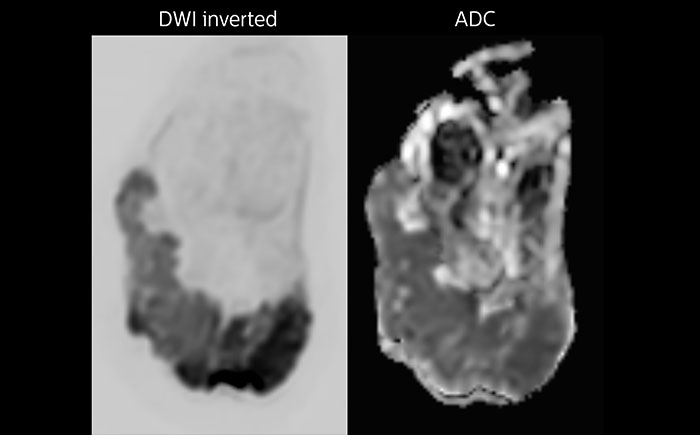

Whole body diffusion

A 61-year-old female with a malignant lymphoma underwent an MRI exam with whole body diffusion weighted imaging (DWIBS) as well as PET. On the images shown, the resolution of DWIBS is better than PET, which allows visualization of the small pelvic lesions and almost no distortion is seen in the neck area.

Whole body diffusion

A 61-year-old female with a malignant lymphoma underwent an MRI exam with whole body diffusion weighted imaging (DWIBS) as well as PET. On the images shown, the resolution of DWIBS is better than PET, which allows visualization of the small pelvic lesions and almost no distortion is seen in the neck area.